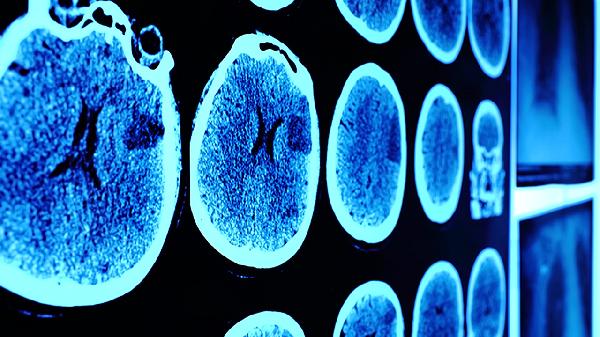

日常应注意保持规律作息,避免过度疲劳和情绪激动。发作后需记录事件细节,包括前驱症状、持续时间和诱发因素。建议随身携带医疗警示卡,定期复查血压、血糖等基础指标。若频繁发作或伴随严重症状,应及时到神经内科或心血管专科就诊,完善脑部CT、核磁共振等相关检查以明确病因。